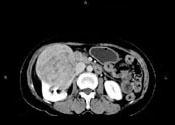

问题 女,57岁,右腰部胀痛6个月余,触及右侧腹部包块2个月,CT平扫及增强如图所示,下列说法正确的是 ( )

选项 A、考虑肿块来源于右肾,是巨大的肾癌,并挤压推移右肝,与其分界欠清 B、考虑肿块来源于右肾,是肾血管平滑肌脂肪瘤,并挤压推移右肝,与其分界欠清 C、增强扫描肿块强化明显,其内可见无强化的低密度坏死灶 D、考虑肿块来源于肝脏,是原发性肝癌,并挤压推移右肾 E、平扫时可见右侧腹部巨大的软组织肿块影,其内可见小片状的低密度影

答案 ACE